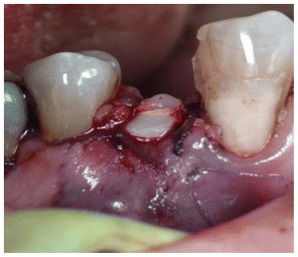

- The guide was placed and checked for correct seating. (Figure 6)

- Harvest was made with piezoelectric instruments.

- The block graft was trimmed extra orally. (Figure 7)